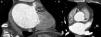

Caso 1Doente do sexo masculino de 20 anos com queixas de dor torácica, referenciado para realização de angioTC cardíaca para exclusão de anomalia das artérias coronárias. O exame revelou coronárias com origem e trajeto dentro da normalidade. As imagens permitiram verificar a passagem de contraste da aurícula esquerda (AE) para a aurícula direita (AD), levantando a suspeita da existência de uma solução de continuidade entre essas cavidades. O ecocardiograma transesofágico confirmou o diagnóstico de comunicação interauricular tipo ostium secundum (Figura 1). O doente foi submetido a encerramento cirúrgico.